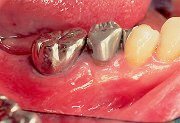

1

| 術直前にアタッチメントレベルを計測しておく(この時点で歯肉は可及的に健康な状態にしておく)。 |

11

| 術後6ヵ月目。術前に8mmのアタッチメントロスが認められた同部への計測が可能となった。今回は、4mmのアタッチメントレベルを認めたことにより、4mmのアタッチメントゲインがあった。 |

| 術後1年目。辺縁歯肉に炎症症状や位置の変化は認められず、術前とほぼ同等の状態が維持されていた。 |